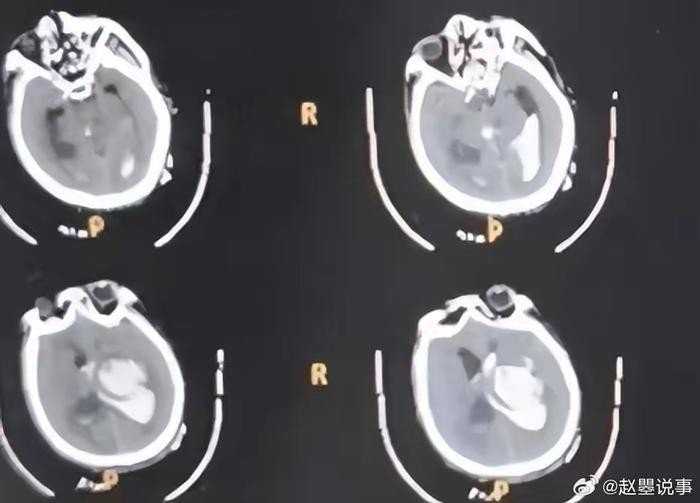

医院经过一番工作后,原来,高大爷之所以晕倒在猪舍里,是突发脑卒中icon。加上高大爷生殖器被啃食后大量出血,病情危急。医院抽调各科室精干力量进行紧急抢救,高大爷算是脱离了生命危险。